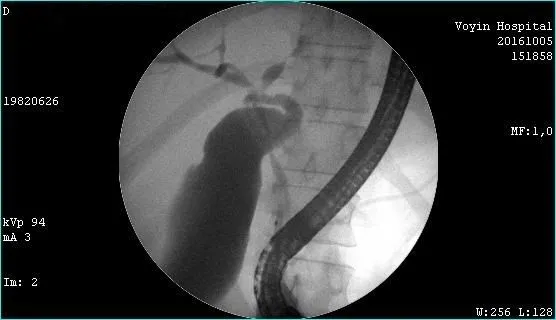

Молодой человек 33 г. Диагноз подтвержден. Стентирован пластиковыми стентами, потом самораскрывающимися. Одномоментно анте и ретроградно - с хорошим результатом. Дальше был поставлен в очередь на трансплантацию. Дальнейшая судьба не известна.